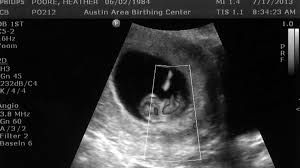

At around 9 weeks your baby now has a newly formed nervous system and is beginning to receive shocks. Depending on your size before. When it comes to pregnancy symptoms you may feel like you ve already reached your limit at 9 weeks pregnant. Baby development at 9 weeks.